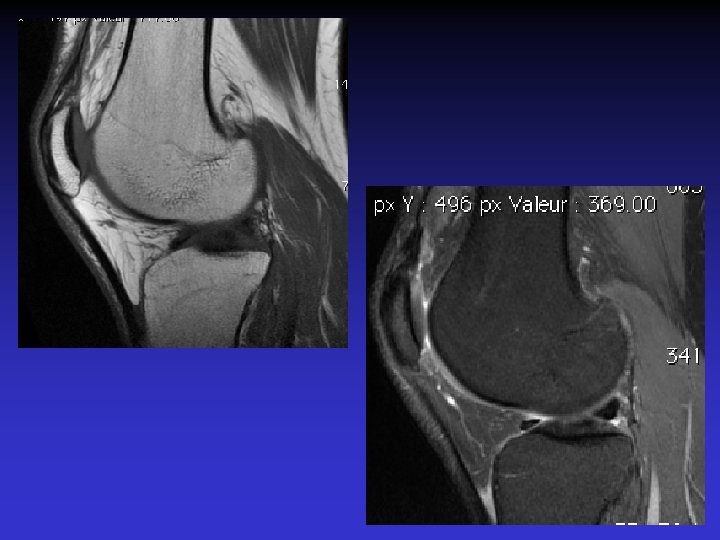

• • • Pas d’épanchement Pas de lésion méniscale Pas de lésion cartilagineuse Pas de lésion osseuse Anomalies du LCA • Épaissi • Hyper signal T 1 et T 2 • Orientation des fibres conservée • Kyste

ASPECT IRM • • Hyposignal TI Hypersignal T 2 Pas de prise du contraste après Gado IV Continuité conservée du LCA+++ avec dilacération des fibres • Aspect en « tige de céleri »